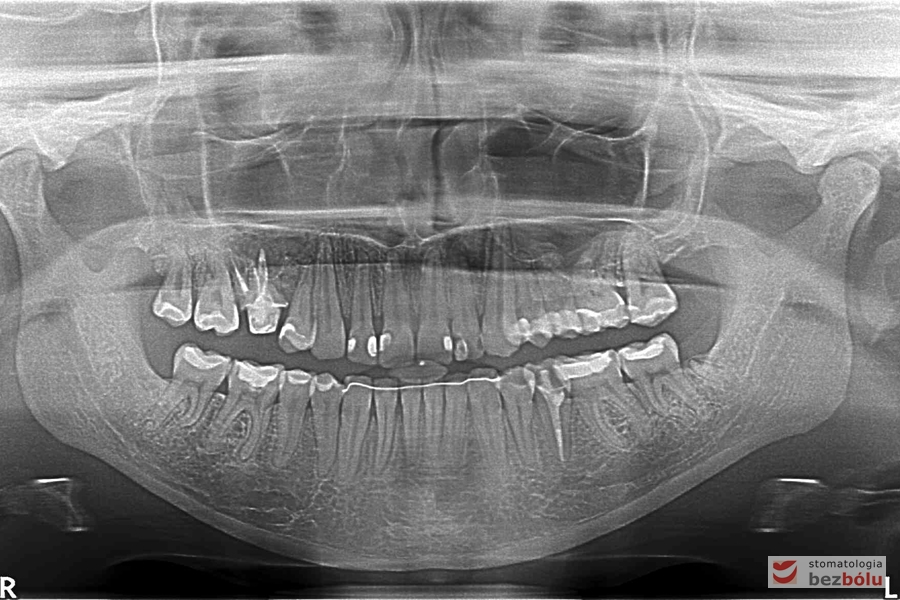

Kontrola radiologiczna - OPG

Kontrola radiologiczna – OPG

Pantomogram - kontrola radiologiczna zaraz po zdjęciu aparatu cienkołukowego

Pantomogram – kontrola radiologiczna zaraz po zdjęciu aparatu cienkołukowego